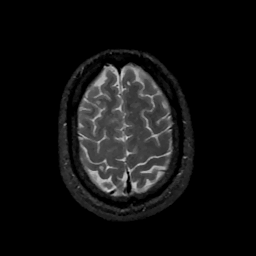

MR Study #11, May 5, 1991 -- Slice #42